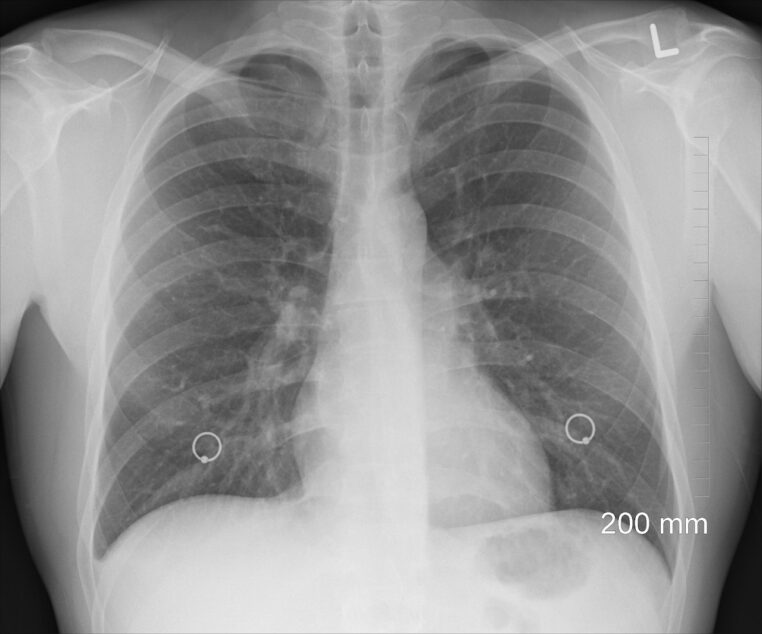

Le coeur à droite

Cela peut paraître étonnant, mais certaines personnes ont leur coeur du côté droit. Cela concerne moins de 1% de la population. Cette particularité porte un nom : le sinus inversus, une maladie qui touche une personne sur 10 000.

Dans le cas de cette maladie, les principaux organes se retrouvent du mauvais côté : le coeur à droite, le foie à gauche… Cependant, cela n’a pas de conséquences sur la santé si l’inversion des organes est complète.